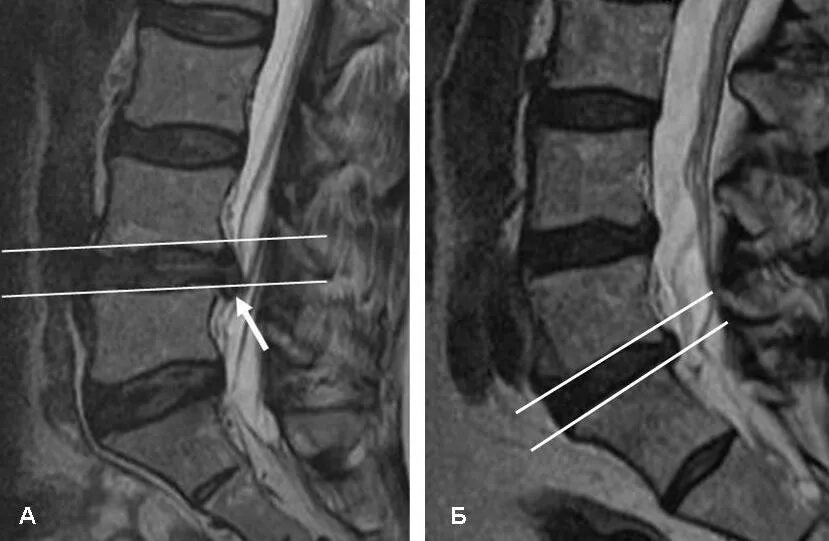

Дорзальная протрузия диска что это такое